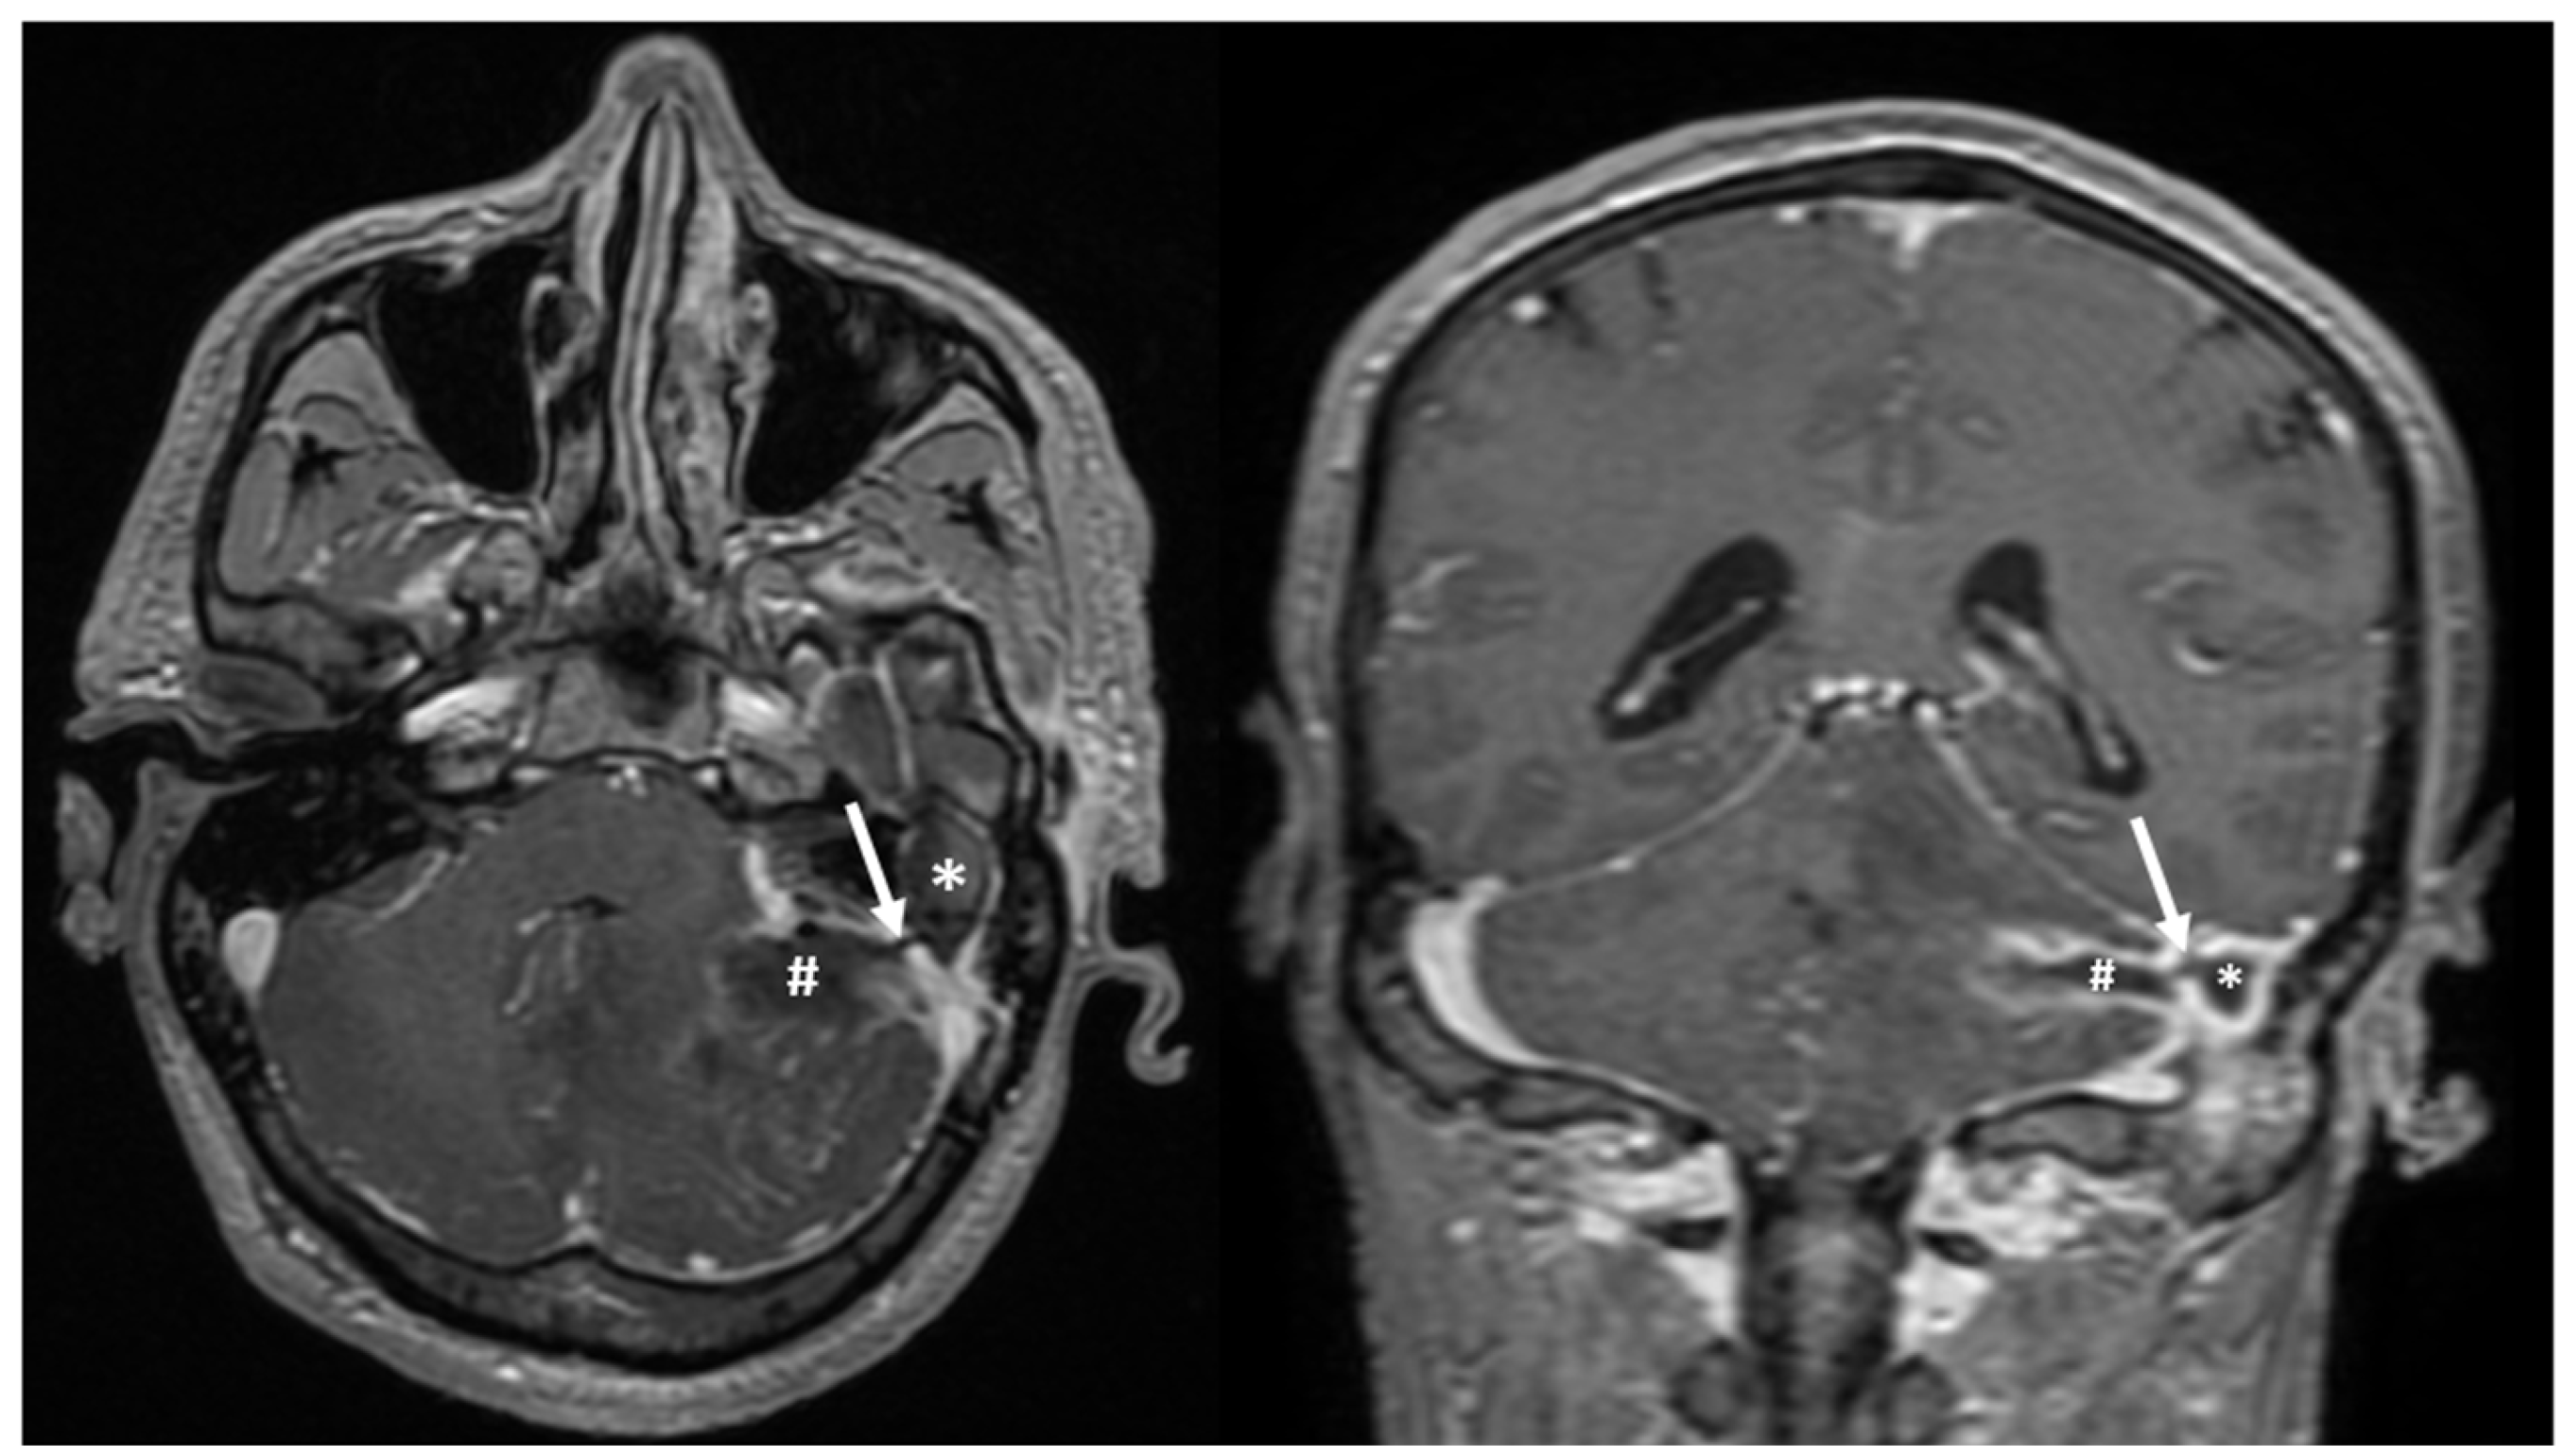

2.2.2. Imaging Studies

3.5. Imaging Studies